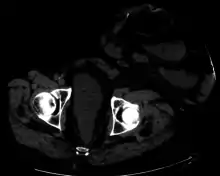

CT scan of same patient, showing intestines within the hernia.

Parastomal hernia (PH) is the most common late complication of stomata through the abdominal wall, occurring in 10-25% of the patients.[10] Prolapse of bowel wall through the stoma occasionally happens and can require reoperation to repair.